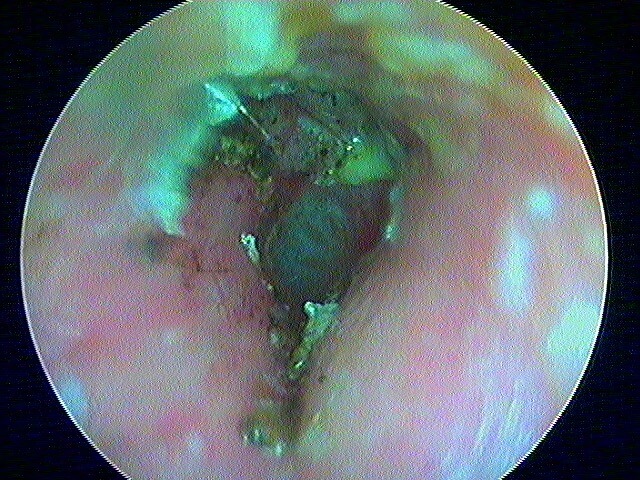

2/5 otite externe mycotique ou otomycose

Dans ma pratique, je vois plus d'otomycose à Aspergillus niger, très caractéristique avec ces points noirs.

La même oreille après aspiration: